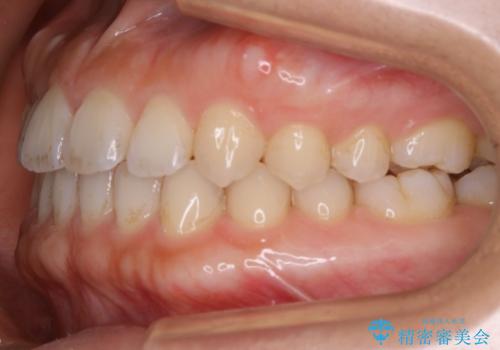

- 矯正治療を主訴にご来院されました。

すきっ歯と噛み合わせの治療をしたいとのことで、インビザラインを用いて矯正治療を行うこととなりました。

すきっ歯の場合、ガタつきを治したりするのに必要なスペースが最初から空いているため、そのスペースを利用して比較的短期間で効率よく治療を進めることが可能となります。

初診時の写真では一見噛み合わせには問題がないように見えても、実際に精密な検査を行うと改善すべき点が見つかる場合も多くあります。

当院では、矯正治療は見た目の改善が主目的ではなく機能面を改善し自然に長持ちする口腔内環境を整えることに重きを置く必要があると考えます。

しかしながら、こちらの理想だけを押し付けるだけが良い治療とは言えないので、患者様と治療のゴールの設定をよく話し合ったうえで方針を決定していくことが最も重要です。